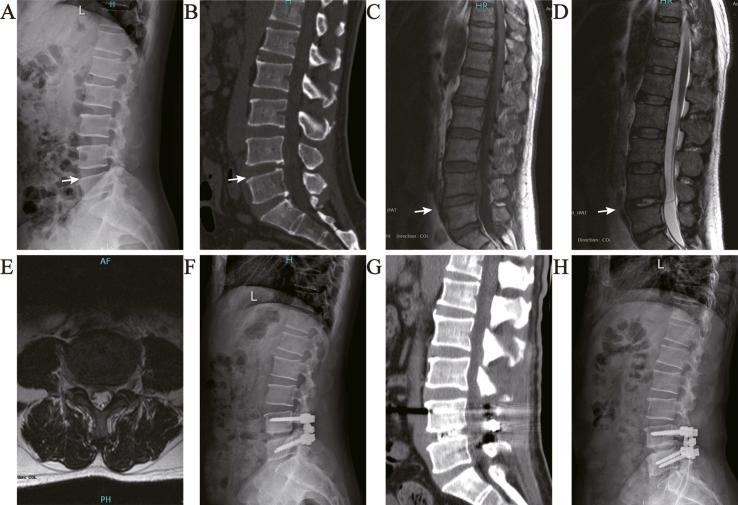

一期后路清创融合联合冲洗引流治疗术后腰椎间盘炎。

One-stage posterior debridement and fusion combined with irrigation and drainage for the treatment of postoperative lumbar spondylodiscitis.

The aim of this study was to evaluate the clinical outcomes of one-stage posterior debridement, interbody fusion, and instrumentation, combined with irrigation and drainage, for treating lumbar spondylodiscitis.

METHODS

The study included 23 patients (13 male and 10 female, mean age: 45 years) who had posterior debridement, interbody fusion, and instrumentation, followed by continuous closed irrigation and drainage for lumbar postoperative spondylodiscitis. The visual analog scale, Oswestry disability index, and lumbar lordosis angle were assessed before and after surgery to evaluate the clinical outcome.

RESULTS

The mean follow-up time was 27 (24-36) months. All patients tolerated the procedure well, and there were no instances of spondylodiscitis recurrence, though a dorsal dermal sinus developed in one patient after surgery. Infection was eliminated, as evidenced by the normalization of the erythrocyte sedimentation rates and C-reactive protein levels. The mean visual analog scale scores were significantly decreased after the operation. The mean lumbar lordosis angle before surgery was 21.61 ± 6.88° and the angle at the final follow-up was 31.61 ± 4.24°. The mean Oswestry disability index scores improved significantly both after the operation and at the follow-up visits (p < 0.05). Bone union was confirmed in all patients at a mean of 8.6 months post-operation, though this was not achieved until 2 years post-operation in one patient. All 3 patients who had neurological deficits showed great improvement at the last follow-up.

CONCLUSION

Surgical management using one-stage posterior debridement, interbody fusion, and instrumentation, followed by continuous closed irrigation and drainage, might be an effective treatment option for lumbar postoperative spondylodiscitis.